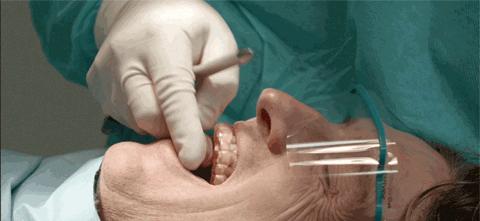

一、单人超声波洁牙口腔护理

超声波全口洁牙 一次

超声波洁牙护理

而洗牙,是借由各种器械来去除这些附着于齿颈与牙龈沟之间的牙结石及牙菌斑,可以减轻牙龈炎、牙周炎的炎症状况。

-牙釉质抛光护理-

牙釉质是牙齿最外层的组织,又是我们身体里坚硬的组织之一。它帮助我们抵御外界对牙齿的入侵,对牙齿起到保护的作用。可以说,它是牙齿的一道保护屏障。

洗牙后还要进行抛光,使牙齿的表面保持光洁如初。从而减缓菌斑及色素的附着和牙石的生成。并且抛光是不会对牙齿造成损伤的哦。